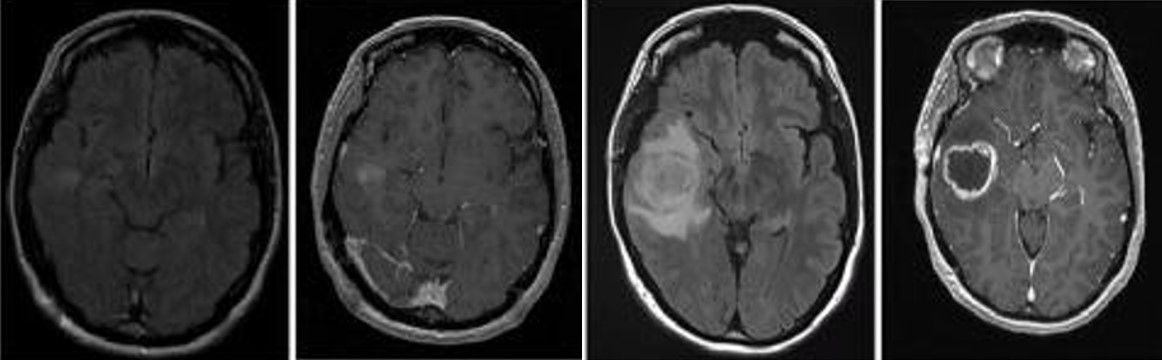

胶质母细胞瘤(Glioblastoma , GBM)是中枢神经系统中比较常见的神经上皮肿瘤,是恶性程度最高的原发性脑肿瘤也是最致命的实体瘤,被世界卫生组织归类为Ⅳ级胶质瘤。GBM 预后差,被诊断后的平均中位生存期为 14个月,其5年生存率为 5%。尽管目前在外科手术,放化疗等医学治疗手段取得了不错的进展,但在延长患者的生存期上仍未取得突破。因此,目前迫切需要筛选鉴定出有效的GBM生物标记物,探索GBM的治疗靶标并解析GBM的发病机理,为GBM的早期诊断及预后评估提供新策略以延缓患者的生存期。

崔红娟教授团队就GBM标志物的筛查、鉴定以及如何管控EGFR在GBM的表达开展了深入研究。首先, GBM患者组织的免疫组化病理检测以及生物信息学分析发现一种能够参与异染色质形成的H3组蛋白甲基化阅读器CBX3(Chromobox 3)在GBM患者中异常高表达,并且与GBM的预后和恶性分级密切相关。功能检测表明了CBX3 在体外和体内显著促进 GBM 细胞的增殖、侵袭和肿瘤发生。从机制上来说,我们通过Ch-IP和Co-IP等一系列生物技术实验证明了CBX3促进GBM 的恶性进展是EGFR 依赖性的,并且进一步揭示了GBM患者发病机理的一条全新的信号通路CBX3-PARK2/STUB1-EGFR。该研究不仅丰富了GBM表观遗传学的研究,也为该信号通路作为GBM潜在治疗靶点的可行性提供了坚实的依据。PA视讯官网2020级博士研究生彭文为第一作者,崔红娟教授为该论文的通讯作者。该研究得到了重庆市自然科学基金和重庆市博士生科研创新项目的支持。